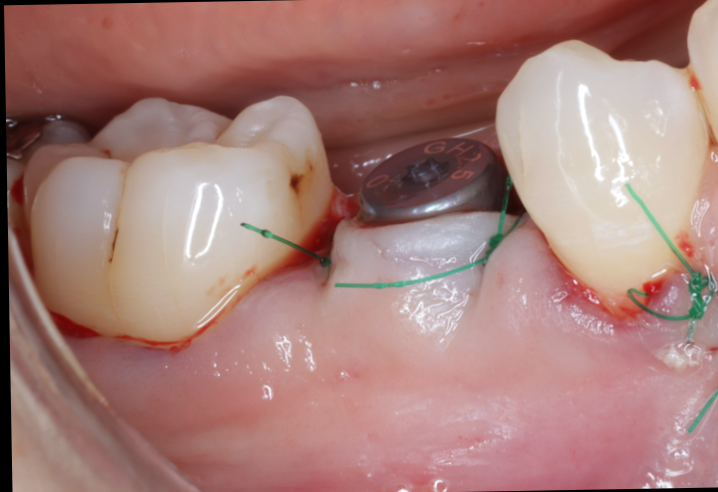

実際の症例紹介

50代女性:

上顎前歯部のインプラント

美容院にお勤めのこの女性は、見た目の問題から仮歯なしでの生活が難しいと判断されていました。

他院では「半年の待機が必要」と診断されたものの、当院では骨の状態と噛み合わせを精密に評価。 BLX+サージカルガイドを使用することで、埋入当日に仮歯の装着を実現しました。 見た目・機能性の両立を求める方にも安心していただける結果となりました。